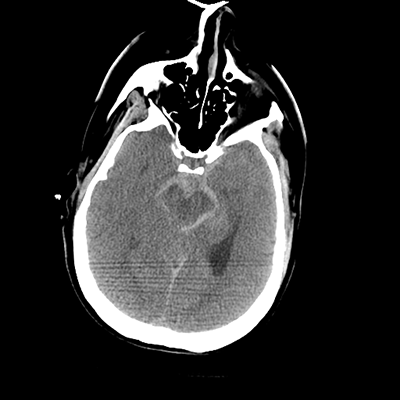

NCHCT

In terms of her neuroimaging, it's clearly abnormal. With the non-contrast head CT, we can see an acute SAH, with blood in the basal cisterns and Sylvian fissures, with some trace blood in the ventricles. The ventricles generally don't look too large, but actually, the temporal horns and atria are visible and larger. So, there's definitely ventriculomegaly that, in combination with her clinical exam, suggests hydrocephalus.